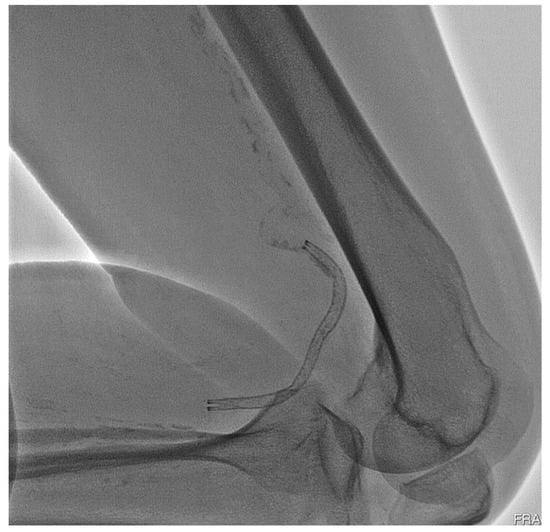

However, peripheral stent could fracture from cyclic loadings due to blood pressures and our body activities after surgery. Such repeated movements continue to oscillate the stent, leading to the risk of fatigue fracture which may cause radial support loss to the arterial wall, in-stent restenosis, thrombus formation, or arterial perforation by sharp strut protrusion [3,4,5]. Partial or complete stent fatigue fractures have been reported in the cases of lower limbs with high fracture rates [6,7,8,9,10]. Peripheral stent fatigue fracture is a known complication of peripheral intervention and is related to increased re-occlusion risk of the treated artery. It has attracted many attentions in the past decades and, therefore, stent fatigue life is a key performance issue for many contemporary peripheral stent designs. Figure 1 shows the deformed shape of an implanted peripheral stent subjected to complex loading conditions when a patient bent his knee.

Figure 1. Deformed shape of a peripheral stent inside a bent patient knee.